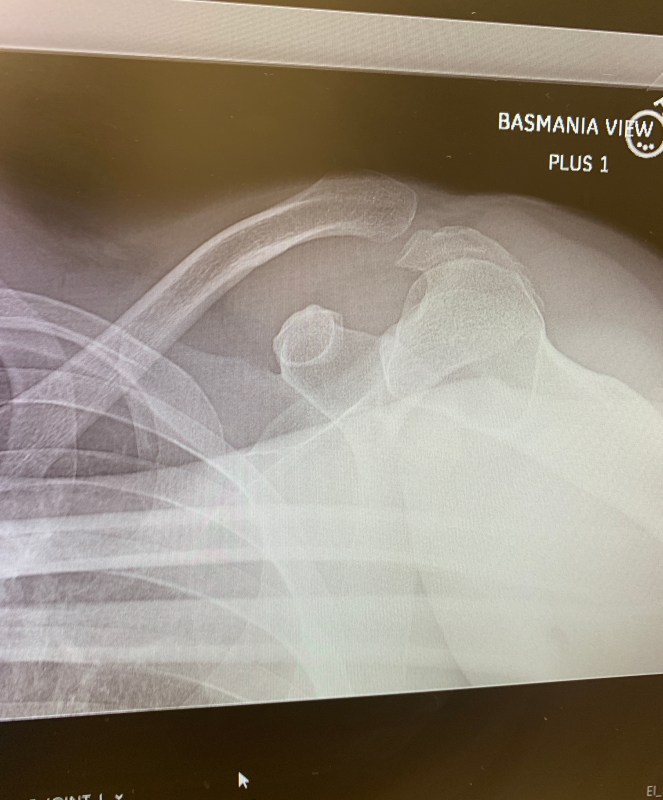

Our old man editor finally gets his wayward clavicle put back into place today at the Hospital For Special Surgery. Frankly, we’ll be glad when this is all over. For the last five days since his “cat”-astrophic crash, all his emails, and half of his published stories, have been filled with the most bizarre typos, mostly because he is dictating everything on his iPhone — and Siri doesn’t speak Grizzled Tabloidese (admittedly, a dying language).

The doctors gave him 100 percent chance of making a full recovery, which, for Kuntzman, means he’ll be back at 75 percent in no time.